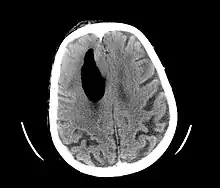

Pneumocephalus

Pneumocephalus is the presence of air or gas within the cranial cavity. It is usually associated with disruption of the skull: after head and facial trauma, tumors of the skull base, after neurosurgery or otorhinolaryngology, and rarely, spontaneously. Pneumocephalus can occur in scuba diving, but is very rare in this context.

| Pneumocephalus and comminuted fracture of the frontal sinus |

If there is a valve mechanism which allows air to enter the skull but prevents it from escaping, a tension pneumocephalus can occur (similar to what can happen in a tension pneumothorax).

CT scans of patients with a tension pneumocephalus typically show air that compresses the frontal lobes of the brain, which results in a tented appearance of the brain in the skull known as the Mount Fuji sign.[1][2][3] The name is derived from the resemblance of the brain to Mount Fuji in Japan, a volcano known for its symmetrical cone. In typical cases, there is a symmetrical depression near the midline (such as the crater of a volcano), due to intact bridging veins.[3] Its occurrence seems to be limited to tension pneumocephalus (not occurring in pneumocephalus without tension).[4] The sign was first described by a team of Japanese neurosurgeons.[5]